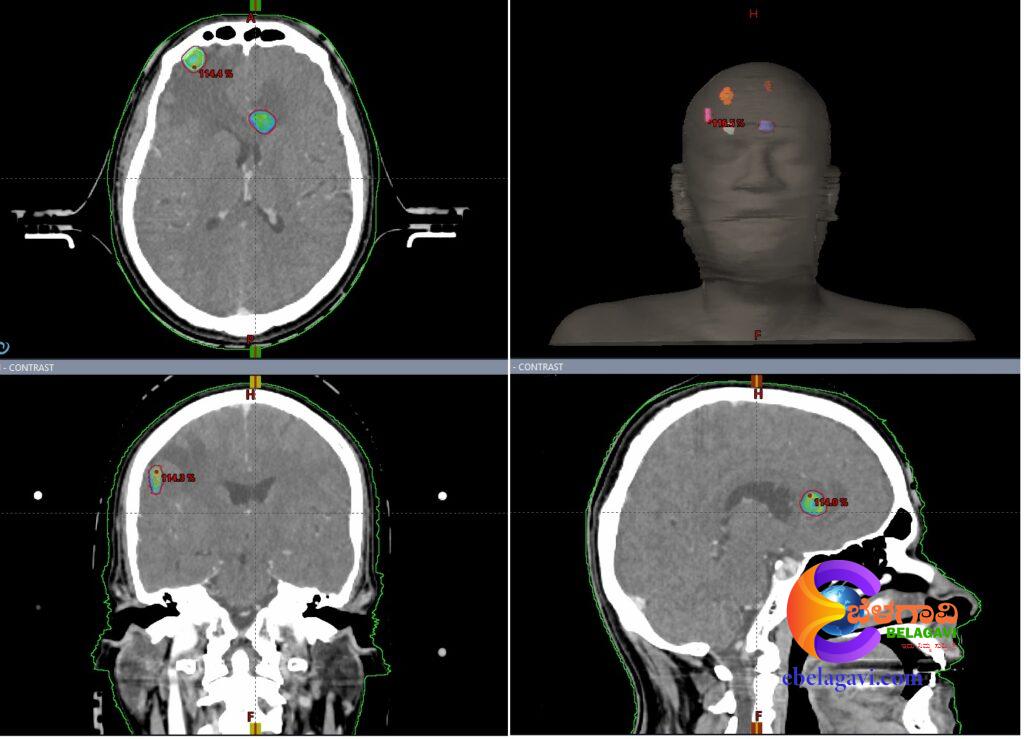

ಮೆದುಳಿನಲ್ಲಿ ದ್ವಿತೀಯ ಹಂತದ ಮೆಟಾಸ್ಟಾಸಿಸ್ ಹಾಗೂ ಪ್ರಥಮ ಹಂತದ ಮೂತ್ರಪಿಂಡದ ಕ್ಯಾನ್ಸರನಿಂದ ಬಳಲುತ್ತಿದ್ದ ರೋಗಿಗೆ ಅತ್ಯಾಧುನಿಕವಾದ ಹೈಪರಆರ್ಕ ವಿಧಾನದ ಮೂಲಕ ಚಿಕಿತ್ಸೆ ನೀಡಲಾಗಿದ್ದು, ಈಗ ಗುಣಮುಖ ಹೊಂದಿದ್ದಾರೆ.

ಹೈಪರ ಆರ್ಕ ಎನ್ನುವದು ಲಿನಾಕ್-ಆಧಾರಿತ ಅತ್ಯಾಧುನಿಕ ತಂತ್ರಜ್ಞಾನವಾದ ವೇರಿಯನ್ ಟ್ರೂಬೀಮ್ ಲೀನಿಯರ್ ವೇಗವರ್ಧಕದಲ್ಲಿ ಕಾರ್ಯನಿರ್ವಹಿಸುತ್ತದೆ. 2.5ಎಂಎಂ ಲೀಫ್, ಮಿಲೇನಿಯಮ್ ಮಲ್ಟಿ-ಲೀಫ್ ಕೊಲಿಮೇಟರ್ (ಎಂಎಲ್ಸಿ) ಅನ್ನು ಒಳಗೊಂಡಿದೆ. 3ಡಿ ಇಮೇಜ್ ತಂತ್ರಜ್ಞಾನದಿಂದ ನಿರ್ದೇಶಿಸಲ್ಪಟ್ಟ ಅತ್ಯಂತ ನಿರ್ದಿ ಷ್ಠವಾದ ಹಾಗೂ ನಿಖರತೆಯನ್ನು ಖಾತ್ರಿಪಡಿಸುವ ಸ್ಟೀರಿಯೊಟಾಕ್ಟಿಕ್ ರೇಡಿಯೊ (ಎಸ್ಆರ್ಎಸ್) ಯೋಜನಾಬದ್ದವಾದ ಚಿಕಿತ್ಸೆ ನೀಡುವಲ್ಲಿ ಅತ್ಯಂತ ಸೂಕ್ಷ್ಮ ಕಿರಣಗಳನ್ನು ಬಳಸಿಕೊಳ್ಳುತ್ತದೆ.

ಅತ್ಯಂತ ಸಂಕೀರ್ಣವಾದ ಕಾರ್ಯವಿಧಾನವನ್ನು ಕೆಲವೇ ಕ್ಷಣಗಳಲ್ಲಿ ಪೂರ್ಣಗೊಳಿಸುವದಲ್ಲದೇ ಚಿಕಿತ್ಸೆಯ ಸಮಯವನ್ನು ಕಡಿಮೆ ಮಾಡುತ್ತದೆ.

ಗಾಮಾ ನೈಫ್ ಅಥವಾ ಸೈಬರ್ನೈಫ್ ವಿಮ್ಯಾಟ ತಂತ್ರಜ್ಞಾನವು ಸಾಮಾನ್ಯವಾಗಿ 45 ನಿಮಿಷಗಳನ್ನು ತೆಗೆದುಕೊಂಡರೆ, ಹೈಪರ ಆರ್ಕ ಕಾರ್ಯವಿಧಾನವು ಸಂಪೂರ್ಣ ಚಿಕಿತ್ಸೆಗಾಗಿ 5 ನಿಮಿಷಗಳನ್ನು ಮಾತ್ರ ತೆಗೆದುಕೊಳ್ಳುತ್ತದೆ. ಕೆಎಲ್ಇ ಕ್ಯಾನ್ಸರ ಆಸ್ಪತ್ರೆಯು ರೆಡಿಯೇಶನ್ ಅಂಕಾಲಾಜಿ ಸೇವೆಗಳಿಗೆ ಹೆಸರುವಾಸಿಯಾಗಿದ್ದು, ಆರೋಗ್ಯ ರಕ್ಷಣೆಯಲ್ಲಿ ಗಮನಾರ್ಹವಾದ ಸೇವೆಯನ್ನು ಕಲ್ಪಿಸುತ್ತಿದೆ. ಮಹಾರಾಷ್ಟ್ರ, ಗೋವಾ ಮತ್ತು ಕನರ್ಾಟಕದಲ್ಲಿ ಪ್ರಥಮವಾದ ಈ ಸೇವೆಯು ಅತ್ಯಾಧುನಿಕ ಕ್ಯಾನ್ಸರ್ ಆರೈಕೆಯನ್ನು ಈ ಭಾಗದ ಜನರಿಗೆ ಕೈಗೆಟಕುವ ದರದಲ್ಲಿ ಸುಲಭವಾಗಿ ಲಭಿಸುವಂತೆ ಮಾಡಲಾಗಿದೆ.